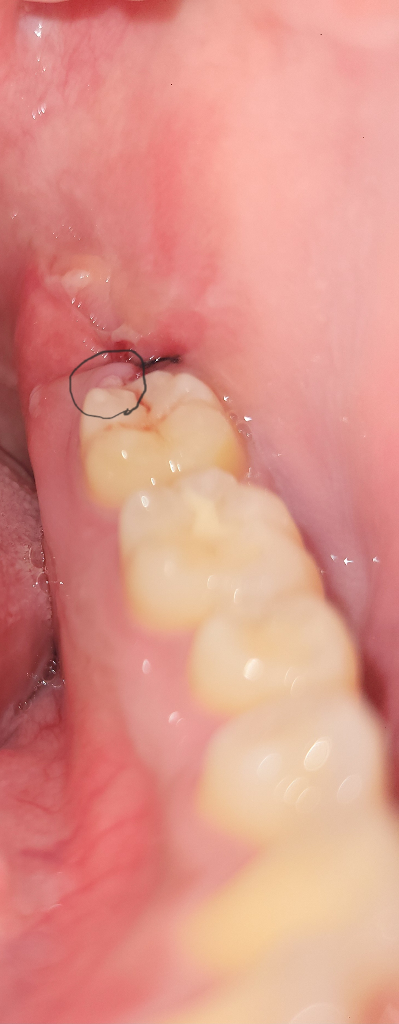

사랑니 발치 후 하루 정도 지났고 동글동글한 작은 구슬같은게 보이는데 그게 뭔지 궁금해요

사랑니 발치 후 하루 정도 지났고 동글동글한 작은 구슬 같은게 보이는데 염증같은건가요 아님 그냥 자연스러운 건지 궁금합니다. 혹시 병원에 가야 하는거면 빠른 답변 부탁드립니다.

현재 발치후에 혈병이 생긴것으로 보이며, 치료가 되어 가는 과정으로 억지로 제거하지 말고 두길 권합니다.

사진에 보이는건 잇몸입니다. 큰문제가 잇는건 아니니 너무 걱정은 하실필요가 없을것같습니다.